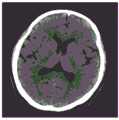

图16A和16B是根据本公开的一些实施例的基于降噪和对比度增强而生成的两个X射线图像;16A and 16B are two X-ray images generated based on noise reduction and contrast enhancement according to some embodiments of the present disclosure;

图17A-17F示出根据本公开的一些实施例基于迭代重建而生成的六个X射线图像;以及17A-17F illustrate six X-ray images generated based on iterative reconstruction according to some embodiments of the present disclosure; and